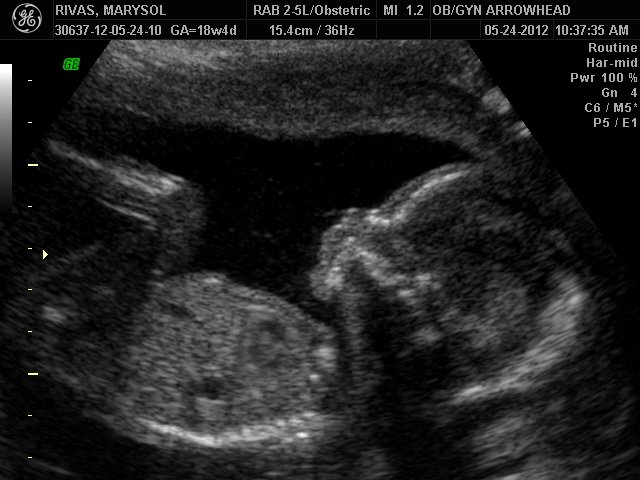

We offer complimentary 3D/4D Ultrasounds to all our OB patients around 30 weeks! The following photos are some examples of our work, shown with permission from our patients.